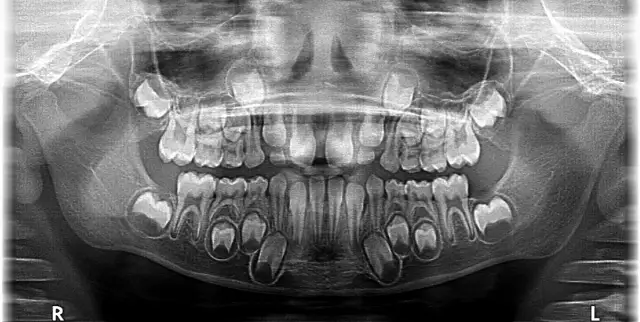

Dzieci w swoim pierwszym etapie życia posiadają dokładnie 20 zębów mlecznych. W skład tego kompletu wchodzi 8 siekaczy, 4 kły oraz 8 trzonowców. Co ciekawe, w uzębieniu mlecznym nie występują zęby przedtrzonowe to ważna różnica w porównaniu do uzębienia stałego. Mniejsza liczba zębów jest w pełni dostosowana do potrzeb rozwijającego się dziecka, jego diety i wielkości szczęki.

Pierwsze zęby mleczne zazwyczaj zaczynają pojawiać się około 6. miesiąca życia, choć oczywiście jest to kwestia indywidualna i może nastąpić nieco wcześniej lub później. Pełen zestaw 20 zębów dziecko powinno mieć w wieku około 2,5 do 3 lat. Proces ich wymiany na zęby stałe rozpoczyna się zazwyczaj około 6. roku życia, co jest naturalnym etapem rozwoju.

Jak już wspomniałem, dorosły człowiek ma od 28 do 32 zębów stałych. Pełne uzębienie stałe składa się z 8 siekaczy, 4 kłów, 8 zębów przedtrzonowych oraz od 8 do 12 zębów trzonowych. Ta różnica w liczbie trzonowców wynika właśnie z obecności lub braku zębów mądrości, czyli ósemek, które nie u każdego się pojawiają.

Proces wymiany zębów mlecznych na stałe to fascynujący mechanizm. Zaczyna się on około 6. roku życia i trwa zazwyczaj do około 12-13. roku życia. Polega na resorpcji, czyli zaniku korzeni zębów mlecznych, co powoduje ich rozchwianie i w końcu wypadanie. W tym samym czasie, pod nimi, rozwijają się i wyrzynają zęby stałe, zajmując ich miejsce.